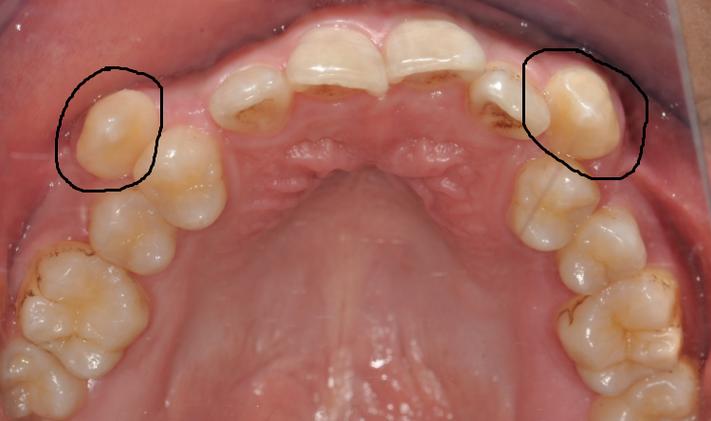

虎牙是口腔中“牙根最长、最坚固”的牙齿之一,位于口角两侧,是牙齿排列中“最后的守门员”,从功能角度看,虎牙具有强大的撕裂食物能力,是咀嚼系统中的重要“切割工具”;从美学角度看,它位于牙弓转折处,支撑着口角和鼻翼的丰满度,对面部轮廓(尤其是“苹果肌”的饱满度)至关重要,虎牙萌出较晚(通常12-13岁),且牙根粗壮、位置靠前,对维持牙弓的稳定性和邻牙排列有不可替代的作用,正畸医生普遍认为,只要虎牙本身健康(无严重龋坏、根尖病变等),且能通过移动纳入牙弓,就应尽力保留,而非轻易拔除。

- 虎牙位置严重异常:如低位、水平阻生虎牙,完全埋伏在颌骨内,且通过外科手术导萌风险过高(如靠近重要神经、血管),或导萌后仍无法建立正常咬合。

需强调的是,以上情况需通过全景片、头颅侧位片、CBCT等影像学检查,结合模型分析、面部测量等综合评估,由经验丰富的正畸医生判断,而非仅凭“牙齿拥挤”就拔虎牙。